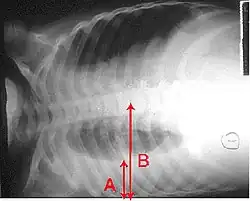

Derrame pleural é a acumulação excessiva de fluido entre as membranas que envolvem o pulmão (cavidade pleural). Uma quantidade excessiva deste fluido pode descompensar a ventilação por limitar a expansão dos pulmões (atelectasia).

A produção aumentada e/ou a reabsorção reduzida faz com que haja uma grande quantidade de líquido no espaço pleural. Grandes derrames pleurais causam insuficiência ventilatória restritiva que se manifesta por “falta de ar” (dispneia).